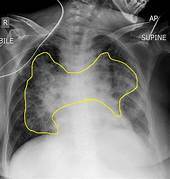

O que esse raio x sugere e quais são as os sinais presentes? Derrame pleural; Imagem em menisco, parabola de Demousiau, opacificação do espaço pleural, deslocamento do diafragma, imagem em menisco, fissuras pleurais e leve deslocamento do mediastino.

Quais são os achados radiológicos do derrame pleural? O que pode causar a doença? -Presença de muito líquido no espaço pleural -Obliteração do seio costofrênico (preenchimento do espaço entre as costelas e o diafragma) -Imagem em menisco -Elevação da cúpula diafragmática -Lawrell pode deslocar o líquido; Tuberculose e neoplasias (Doença pleural), insuficiência cardíaca e congestiva (Doença sistêmica)